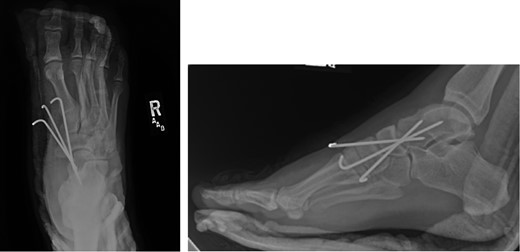

Once general anesthesia was induced, closed reduction was attempted using axial traction with the knee in flexion. Closed reduction was unsuccessful once again (Fig. 3) so the decision was made to attempt open reduction. An anteromedial approach was used dissect down to the talonavicular joint. Retractors were placed with care to avoid injury to tibialis anterior tendon or superficial peroneal nerve. The joint capsule was seen to be disrupted and further exposure revealed a thin, coronal fracture of the anteromedial aspect of the talar head measuring roughly 2 cm in length and 6 mm in thickness (Fig. 4). Once this fragment was removed, the subtalar and talonavicular joints were easily reduced. It was thought that this incarcerated fragment was the likely cause for the unsuccessful closed reduction. The talar head fragment was unamendable for stabilization due to its small size with poor healing potential, thus it was removed. The talonavicular joint was then percutaneously pinned in retrograde fashion with three K-wires (Fig. 5) to maintain anatomic reduction of the subtalar and talonavicular joints and the foot was splinted. At 2 weeks follow-up the patient was doing well and radiographs revealed no interval loss of reduction (Fig. 6).

Some studies suggest obtaining a CT scan of the ankle postreduction to check anatomic reduction as well as assess for other fractures [8, 9]. In our case, we did not obtain a postreduction CT scan. The subtalar and talonavicular joint were well visualized intraoperatively and were found to have no other associated fractures. In addition, anatomic reduction was obtained and under direct visualization and confirmed with fluoroscopy. Due to residual instability following reduction, K-wires were used to stabilize and hold the reduction. K-wire transfixation is supported in the literature for subtalar dislocations which tend to redislocate [10]. In other cases, where the joint is stable after reduction, there is no need for fixation.

In the case report presented, a medially displaced subtalar dislocation was found to be irreducible using closed techniques. During open reduction, an anteromedial talar head fracture fragment was found be blocking the reduction. Once removed, the dislocation was easily reduced, but still unstable. Three K-wires retrograde percutaneous K-wires were placed across the talonavicular joint to hold the reduction. Short-term follow-up has been unremarkable.